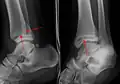

Sur les radiographies, on peut voir une fracture de la malléole médiale, de la malléole latérale et/ou du bord antéro-postérieur du tibia distal. Le bord postérieur (appelé malléole postérieure) est beaucoup plus fréquemment lésé que la face antérieure du tibia distal. Si les malléoles latérale et médiale sont brisées, on parle de fracture bimalléolaire (certaines d'entre elles sont appelées fractures de Pott (en)). Si la malléole postérieure est également fracturée, on parle de fracture trimalléolaire.[réf. nécessaire]

Vue AP en contrainte manuelle montrant une déchirure du ligament deltoïde.

Une fracture triplane de la cheville vue sur une radiographie standard